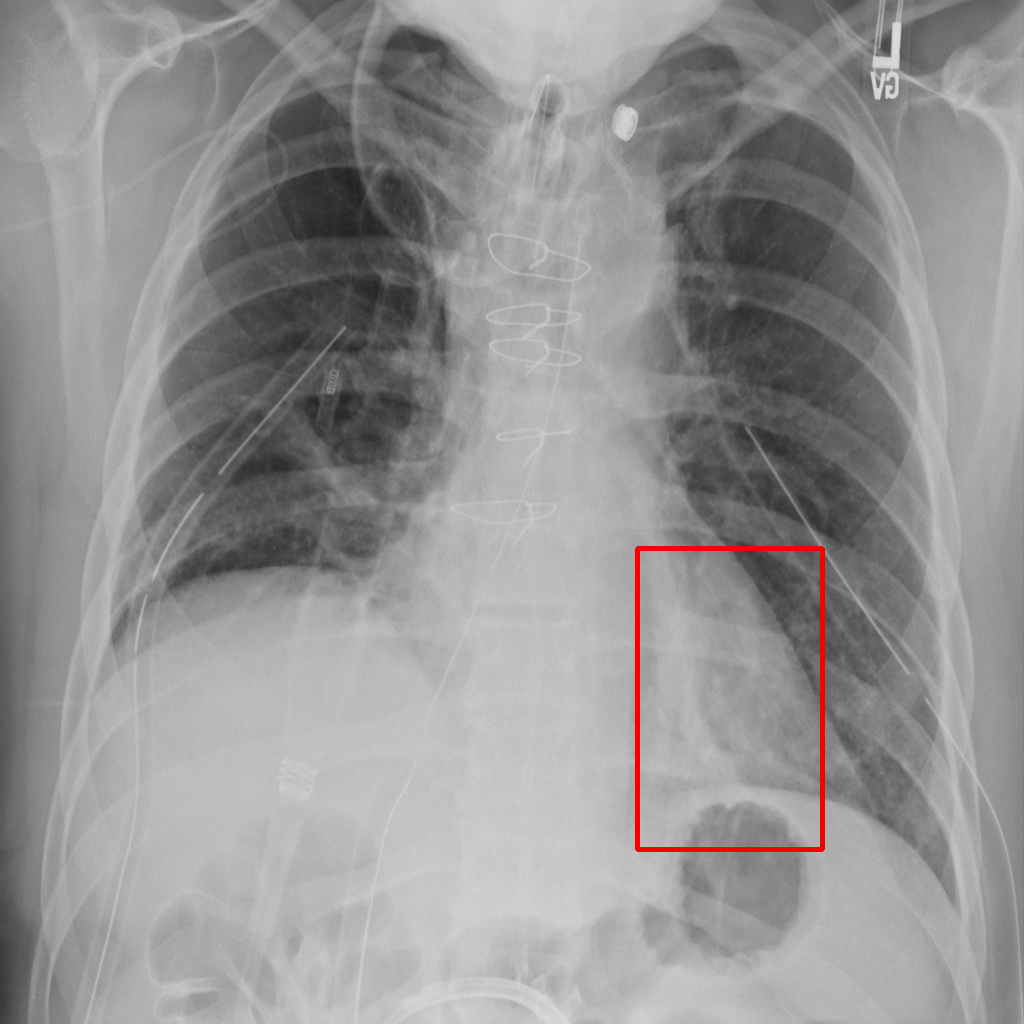

Object Rotation

X-ray GMAIMMbench Disease Diagnosis

Object Rotation - L0 (Original)

L0

L0 (Original)

Object Rotation - L1 (Moderate)

L1

L1 (Moderate)

Object Rotation - L2 (Severe)

L2

L2 (Severe)

Question

Given the boxed region in the X-ray image, which abnormality is the image most indicative of?

A pneumothorax B pulmonary fibrosis C bone fracture D pleural effusion

Ground Truth: A. pneumothorax